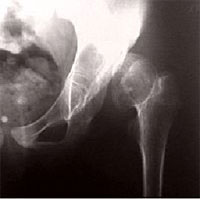

Патологический вывих бедра и неоартроз при врождённом вывихе бедра

Неоартроз. Врождённый вывих бедра.

Если вывих бедренной кости не устранен, то, следуя известному биологическому закону «функция определяет форму», растущие кости таза и бедренная кость изменяются, приспосабливаясь к новым условиям нагрузки. Головка бедренной кости теряет обычную шаровидную форму и уплощается. Пустая вертлужная впадина уменьшается в размерах, а в месте нового расположения головки бедренной кости (в области крыла подвздошной кости) формируется новая суставная впадина. Вновь образованный сустав называют «неоартроз». Это — неполноценный сустав, однако он десятки лет «служит» тем пациентам, которым по разным причинам не был устранен врожденный вывих бедра.

При неправильном лечении врождённого вывиха бедра в детском возрасте, бедренная кость смещается вверх за пределы вертлужной впадины и упирается в тазовую кость.